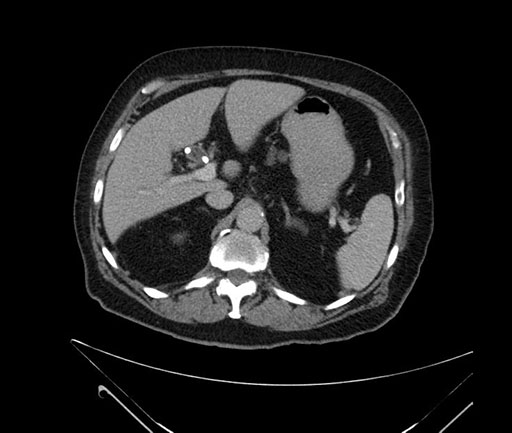

Imaging Analysis

Look through the patient's CT scan to identify any areas of concern for the necessary procedure.

Based on your CT findings, which issue(s) would give reason for "planned slowing down moment(s)" in this case?